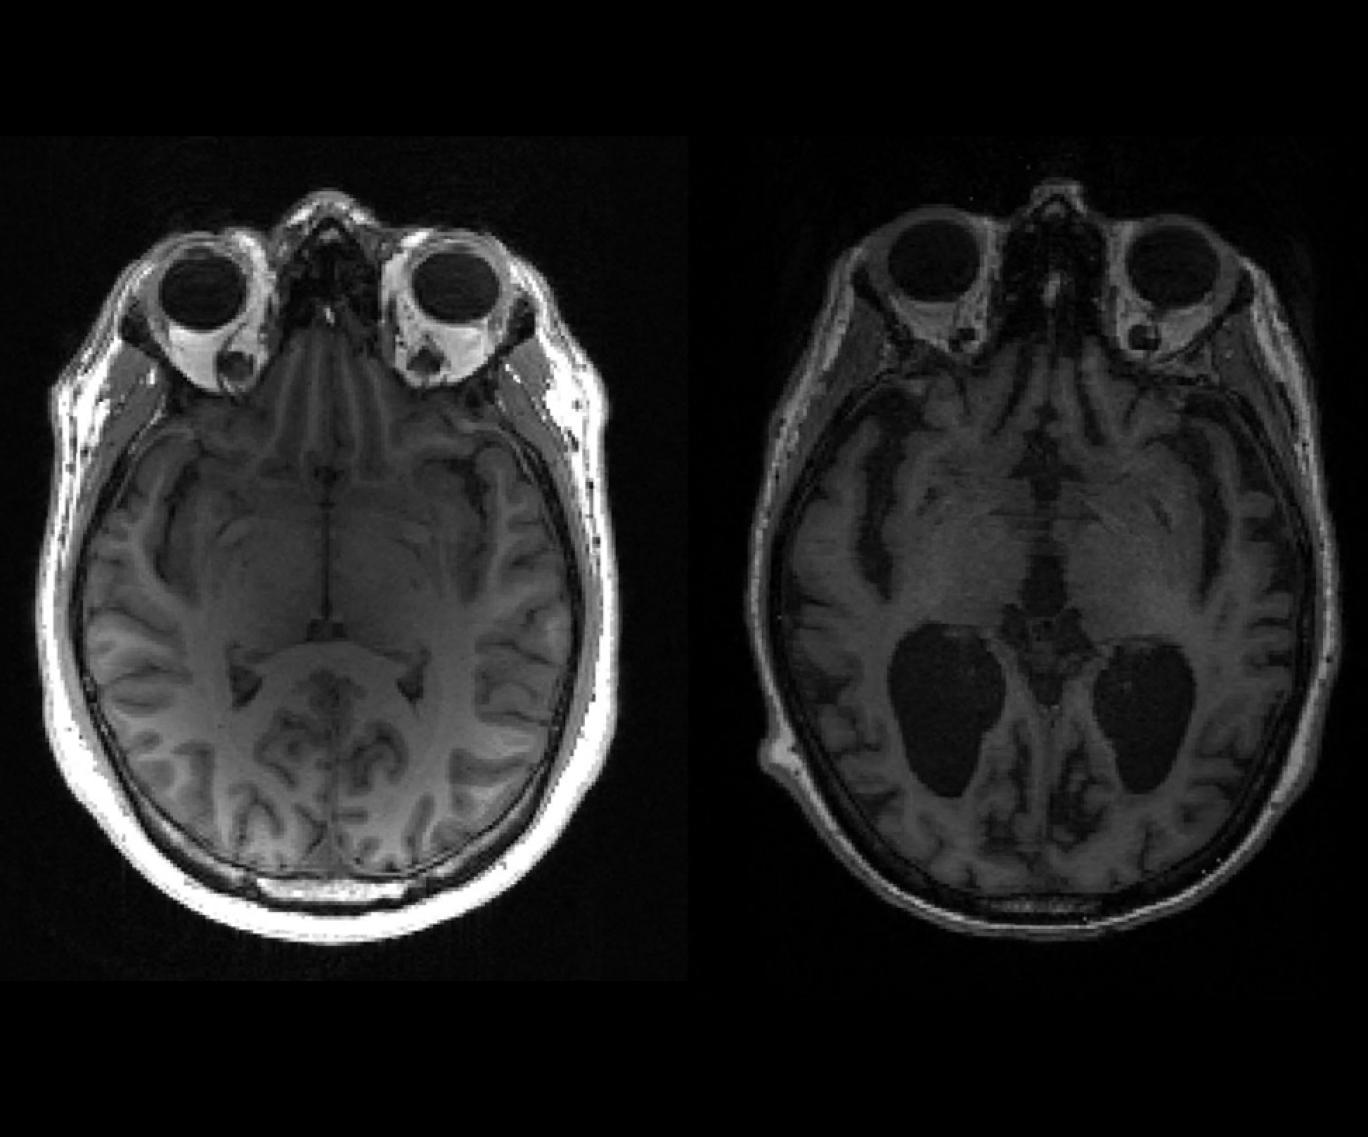

هر دو دارو پادتنهایی مصنوعی شبیه پادتنهای تولیدی دستگاه ایمنی بدناند و برای از بین بردن نوعی پروتئین بیفایده و «چسبنده» به نام آمیلوئید که در مغز افراد مبتلا به آلزایمر تجمع میکند، طراحی شدهاند.

این داروها توانایی پاکسازی کامل آمیلوئیدهای جمعشده را نشان دادند و اعتقاد بر این است که همین دلیل اثربخشی آنها است.

اما اثر داروها، حداقل در مدت زمان این آزمایشها کم بود. هنوز هیچ دارویی موفق به متوقف کردن آلزایمز نشده است، چه رسد به معکوس کردن اثرات آن.